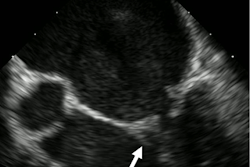

Martin's condition worsened. On October 18, he was diagnosed with endocarditis. Doctors also discovered that the aching muscle in Martin's leg was an infected clot in his femoral artery. He underwent a five-hour surgery to have it removed.

Though Martin continued to be treated with medication, chest scans revealed his heart was severely damaged. On October 21, he underwent a seven-hour open-heart surgery to replace his aortic valve and repair the mitral valve. Since the gums are a bacterial roadway to the heart, doctors believe the gum infection caused the heart damage.